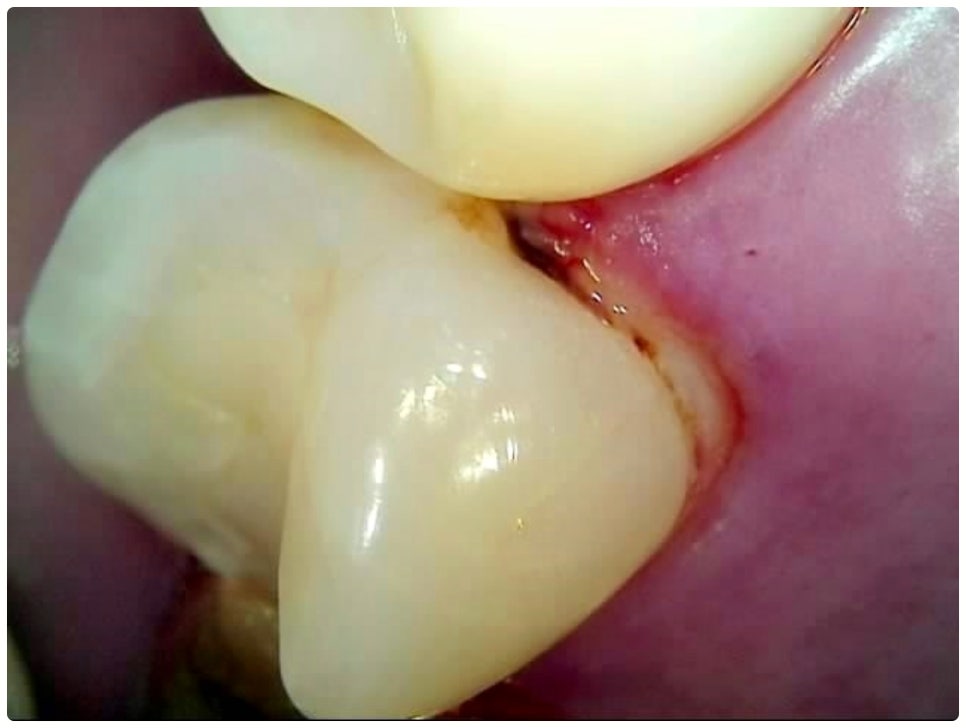

그렇기 때문에 많은 분들이 일반적으로 시린 통증을 느낄 때 치과를 방문하게 되는데, 이 때는 이미 충치균이 치아의 단단한 겉면인 법랑질을 뚫고 상아질까지 침투한 단계일 가능성이 높으니 더 늦기 전에 바로 필요한 처치를 해 주실 필요가 있습니다. 상황에 따라 다르지만 보통 이 단계에서는 레진으로 직접 때워주는 치료가 적합하지 않은 경우가 많기 때문에 그럴 때는 충치치료종류 중 인레이 온레이와 같은 보철물을 이용하여 도움을 받을 수 있는데요. 이러한 치료는 손상된 부위를 깔끔하게 삭제한 후에 그 범위와 정도에 따라 빈 공간에 맞춤 제작한 보철물을 채워넣는 것으로 (인레이는 상대적으로 깊고 좁은 부위에, 온레이는 교두를 포함한 좀 더 넓은 부위에 적용), 재질 역시 다양한 가운데 치아의 위치 및 역할, 그리고 환자분들의 경제적 상황 등 여러 가지를 고려하여 가장 잘 맞는 것으로 선택하면 되니 꼼꼼한 검진 후 담당의 선생님과 각 재질의 장단점에 대해 사전 상담을 충분하게 해 보시고 신중한 결정을 내리시길 권유드리고 있어요.

교정을 하고 있거나 사후 유지 장치를 부착한 경우, 보철물 치료를 받은지 오랜 시간이 지나 보철물과 치아 사이 틈이 생겼거나 잇몸 질환 및 치경부 마모증 등으로 인해 치근이 드러난 경우에는 더욱 치석이 빨리 쌓이고 충치 역시 쉽게 발생할 가능성이 높아지므로 스케일링 치료에 좀 더 신경 쓰는 게 좋을 거예요. 일반적으로 성인의 경우 1년에 한 번 또는 두 번 정도 스케일링 치료를 받는 것이 보통이지만, 이와 같이 좀 더 주의가 필요한 상황이라면 1년에 3~4번 정도로 주기를 짧게 하실 필요가 있어요. 1년에 한 번은 건강 보험을 통해 보다 합리적인 가격으로 스케일링 치료를 받으실 수 있으니 만약 이용해 보신 적이 없으시다면 올해가 가기 전에 관리 및 검진을 위해 치과에 내원해 보시길 권유드리고 있습니다.